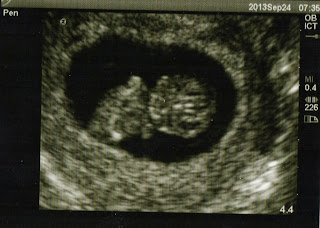

We had our second doctor appointment today! We talked to a nurse practitioner and she did my pap smear (ugh) and an ultrasound! All of my blood work came back healthy, nothing wrong with me. The ultrasound was amazing! We saw LBD, who's now the size of a kumquat or Habanero pepper, and even saw the heart beating! We got five of the ultrasound pictures, but I only scanned one of them: